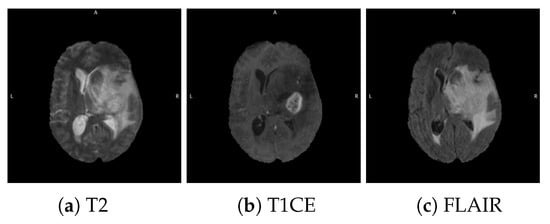

4.2.1. Ensemble of Ensembles Using T1CE, T2, and FLAIR MRIs

4.2.2. Multi-Branch CNN Training with Multi-Sequence 3D MRIs